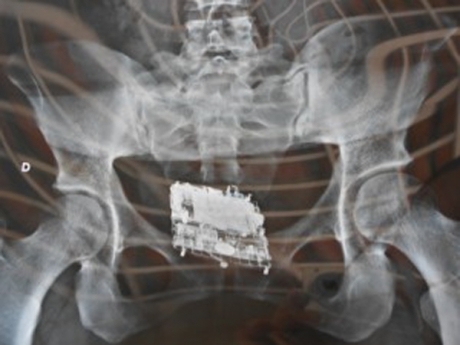

De acordo com o diretor, a agente penitenciária da Cadeia de Quixadá percebeu um escorrimento na região genital de uma auxiliar doméstica. Ela pretendia visitar o marido. Para evitar algum constrangimento desnecessário, já que ela negava a existência de qualquer objeto introduzido no seu corpo, a alternativa encontrada foi conduzi-la até o Hospital Municipal Eudásio Barroso, onde foi feito o Raio X. Quando a chapa foi revelada a equipe da Cadeia Pública ficou surpresa. Havia um aparelho celular no ânus dela. O objeto mede 5cm de largura por 6,5cm de comprimento. Estava num preservativo.